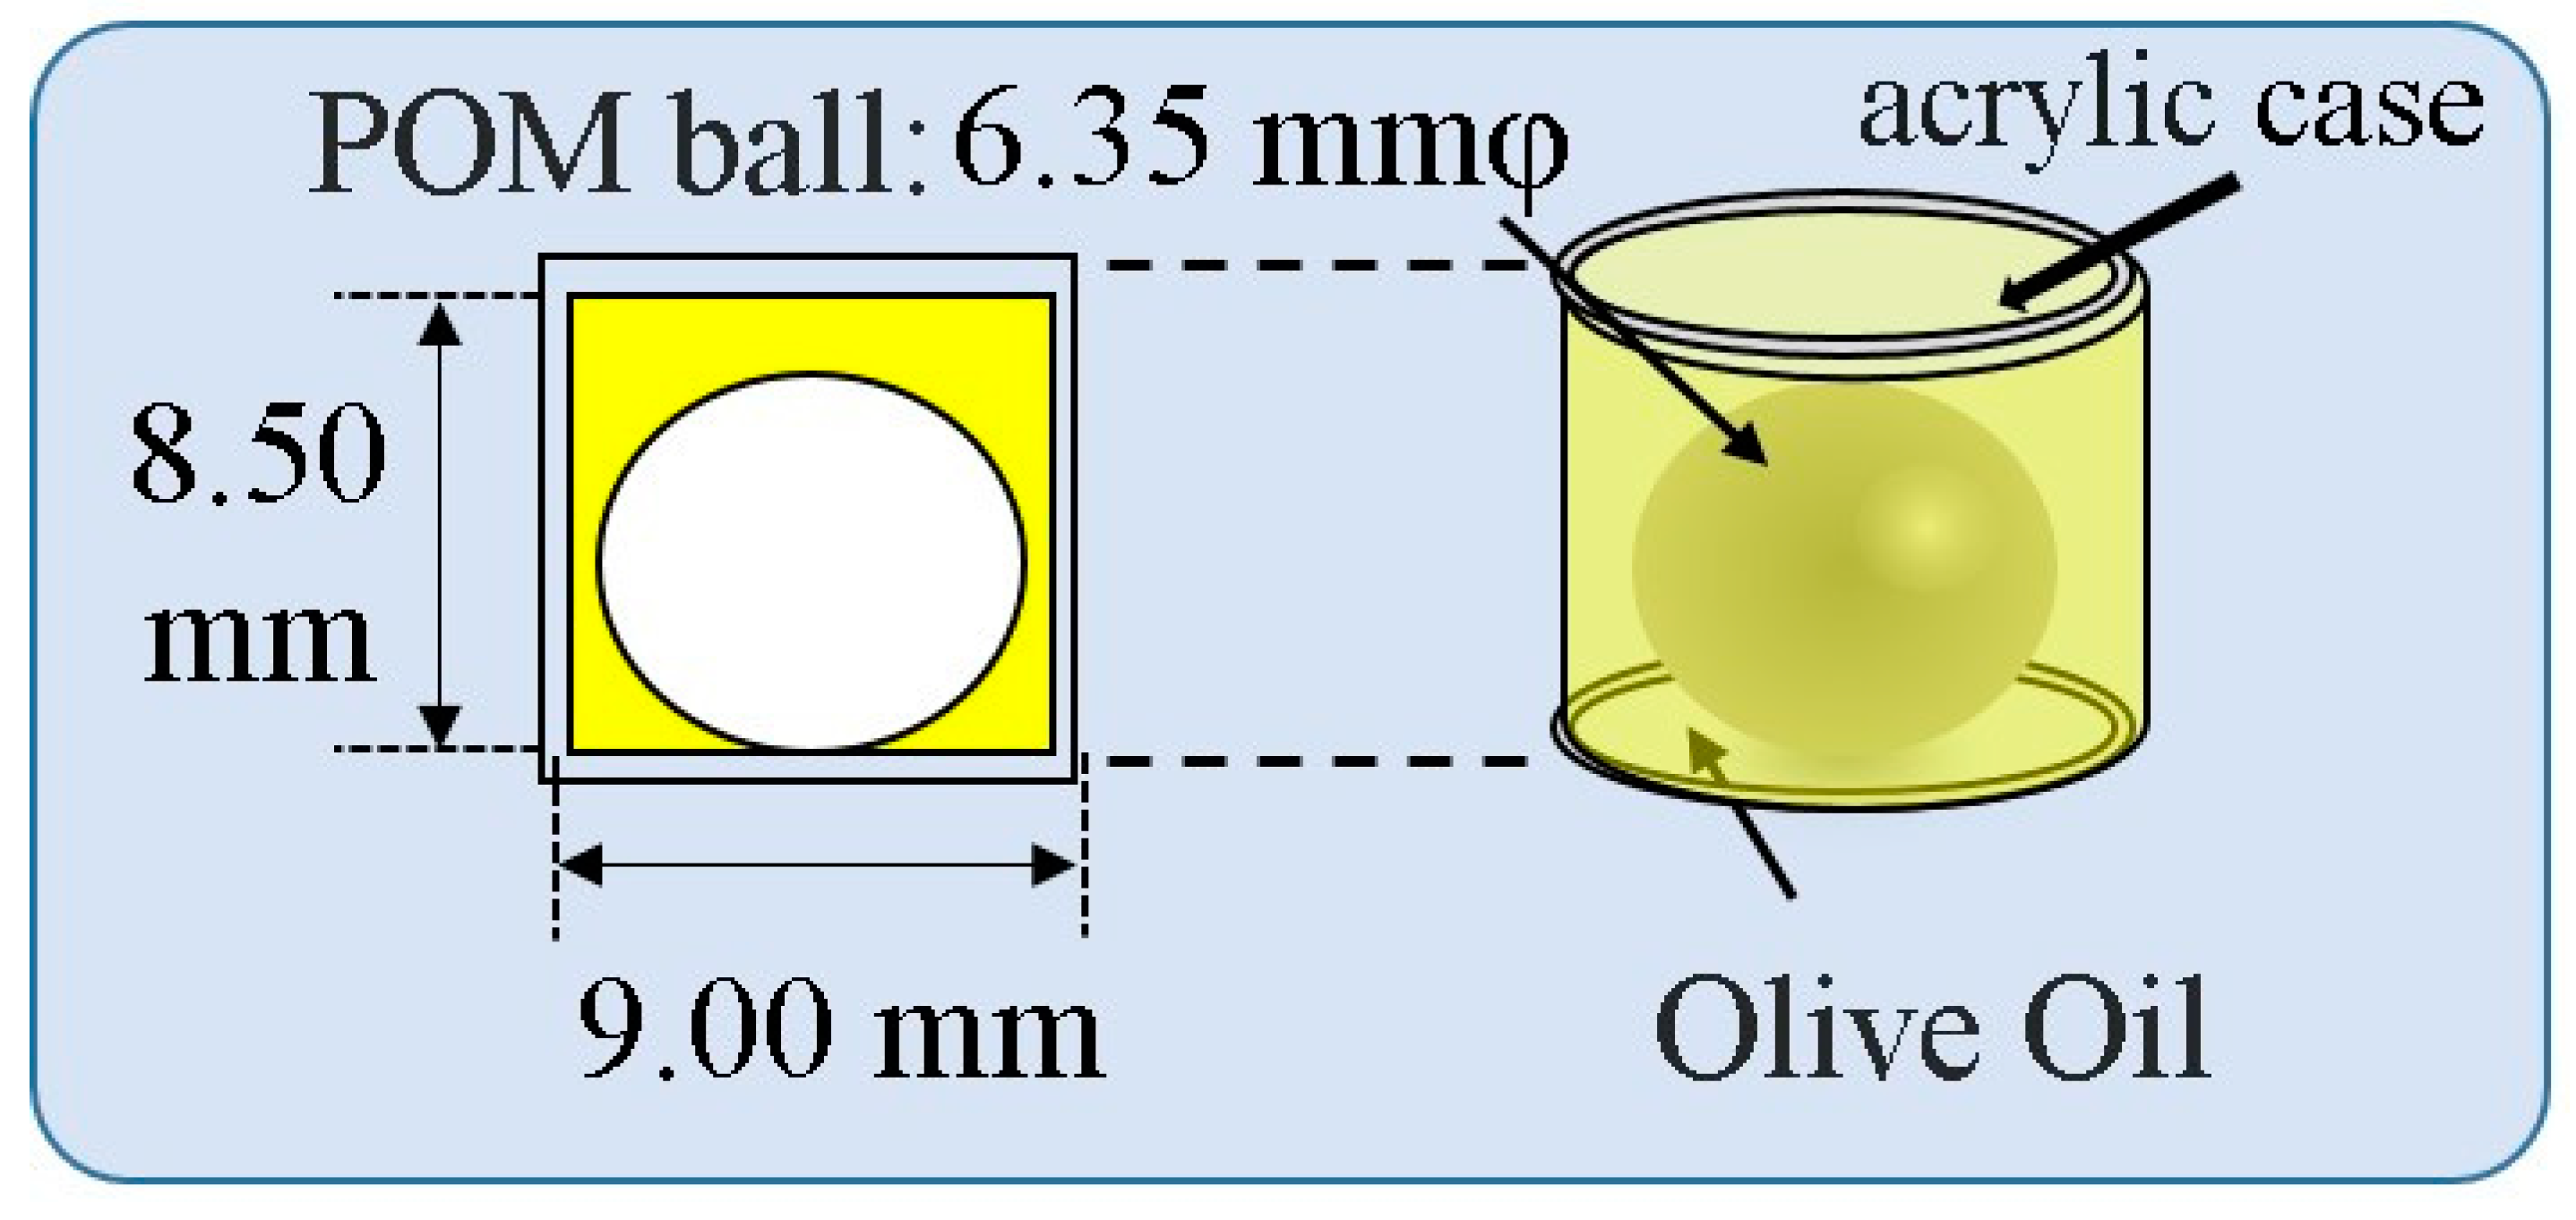

2.3. Measurement Method of Sound Velocity in Human Crus